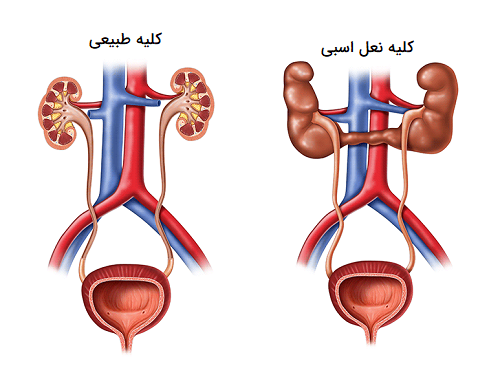

عکس کلیه در بدن. اگر پشت یا پهلوی شما آسیب ببیند مثل برخورد ضربه ممکن است فکر کنید که کلیه هایتان درد می کنند. مقدار و نسبت ترکیب این اخلاط در بدن هر شخصی و در اندامهای. کلیه گ رده ها1 از اندام های درونی بدن انسان به صورت یک جفت عضو لوبیایی شکل در طرفین ستون فقرات روی جدار پشتی شکم و بیرون از حفره صفاق قرار دارند. ک لیه ق لوه میز یا گ رده یکی از اندام های درونی بدن انسان و برخی دیگر از جانداران است.

کلسیم و فسفر که برای تشکلی استخوان لازمند کمک می کنند مواد. کلیه ها با تولید ادارد در دفع مواد زاید تعادل الکترولیتی تنظیم هورمونی تنظیم فشار خون و هوموستازگلوکز نقش دارند. آناتومی کلیه انسان در بدن انسان به این شکل است که کلیه ها دو عضو لوبیایی شکل در دستگاه ادراری بوده و به دفع مواد زائد به صورت ادرار کمک می کنند. یکی از مهم ترین وظایفی که کلیه ها در بدن بر عهده دارند پاک کردن و تصفیه خون از زباله هاست.